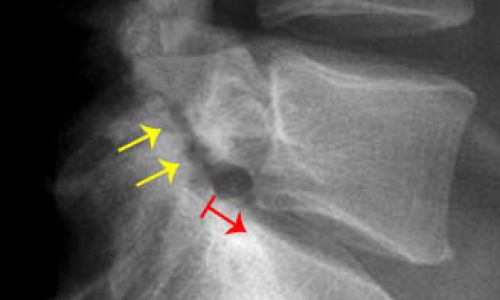

Σπονδυλόλυση

Είναι η λύση της συνέχειας του οστού μεταξύ άνω και κάτω αρθρικής απόφυσης του σπονδυλικού τόξου. Εμφανίζεται συνηθέστερα ως αποτέλεσμα κατάγματος, ισχυρού τραυματισμού ή κληρονομικής προδιάθεσης ή εκφυλισμού σε μεγαλύτερης ηλικίας ασθενείς.

Ο Ορθοπαιδικός θα αποφασίσει ανάλογα με τη βαρύτητα και την κλινική εικόνα, ποια θεραπευτική αγωγή θα ακολουθηθεί που στις περισσότερες περιπτώσεις είναι συντηρητική.